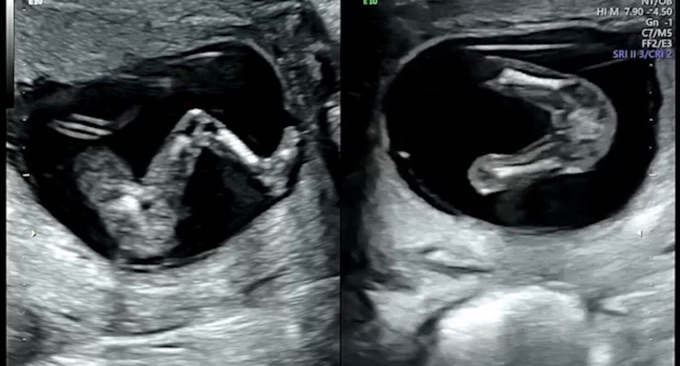

12주 초음파인데요 딸일까요 아들일까요?

아직 12주라 확실하진 않다고 하는데요

내심 딸을 바래서 이리보고 저리 보고 있어요

고수님들 알려주세요~